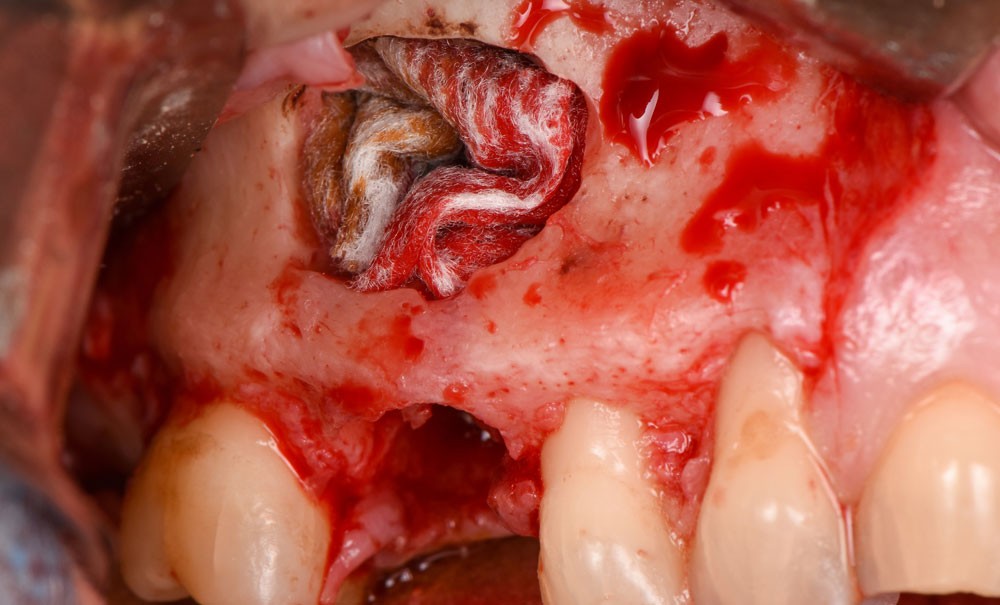

Dans la majorité des cas, l’énucléation kystique s’accompagne de l’extraction de la dent causale. Toutefois, en présence de dent conservable sur le plan prothétique, une chirurgie endodontique (obturation a retro…